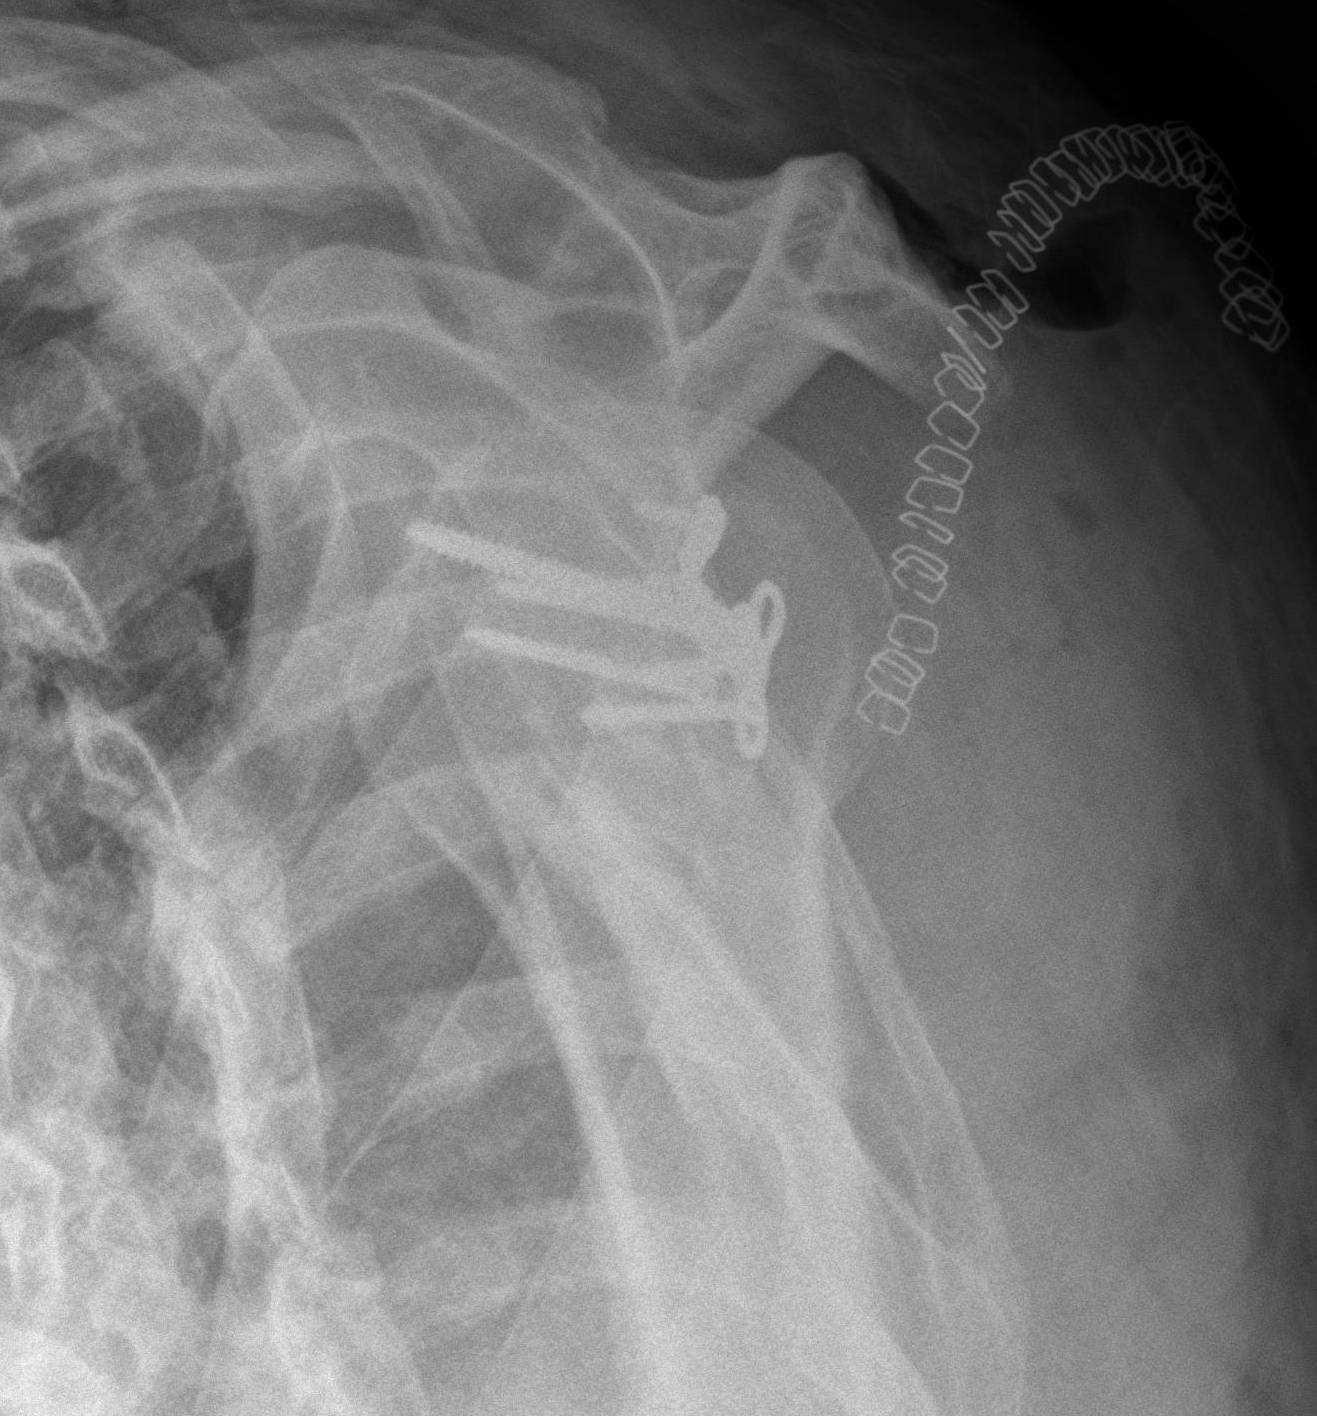

from www.svuhradiology.ie

Scapular fracture Radiology at St. Vincent's University Hospital